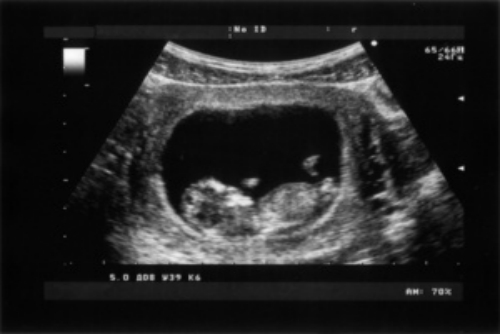

產(chǎn)科超聲檢查,是利用超聲波技術(shù)對(duì)妊娠相關(guān)疾病進(jìn)行的檢查。產(chǎn)科超聲檢查報(bào)告單有很多,常見的有孕周、胎心、胎位、羊水、胎盤等。根據(jù)報(bào)告單的提示,判斷胎兒是否存活,以及胎兒的發(fā)育情況,同時(shí)也可以對(duì)孕婦的分娩方式進(jìn)行選擇。

超聲檢測(cè)1